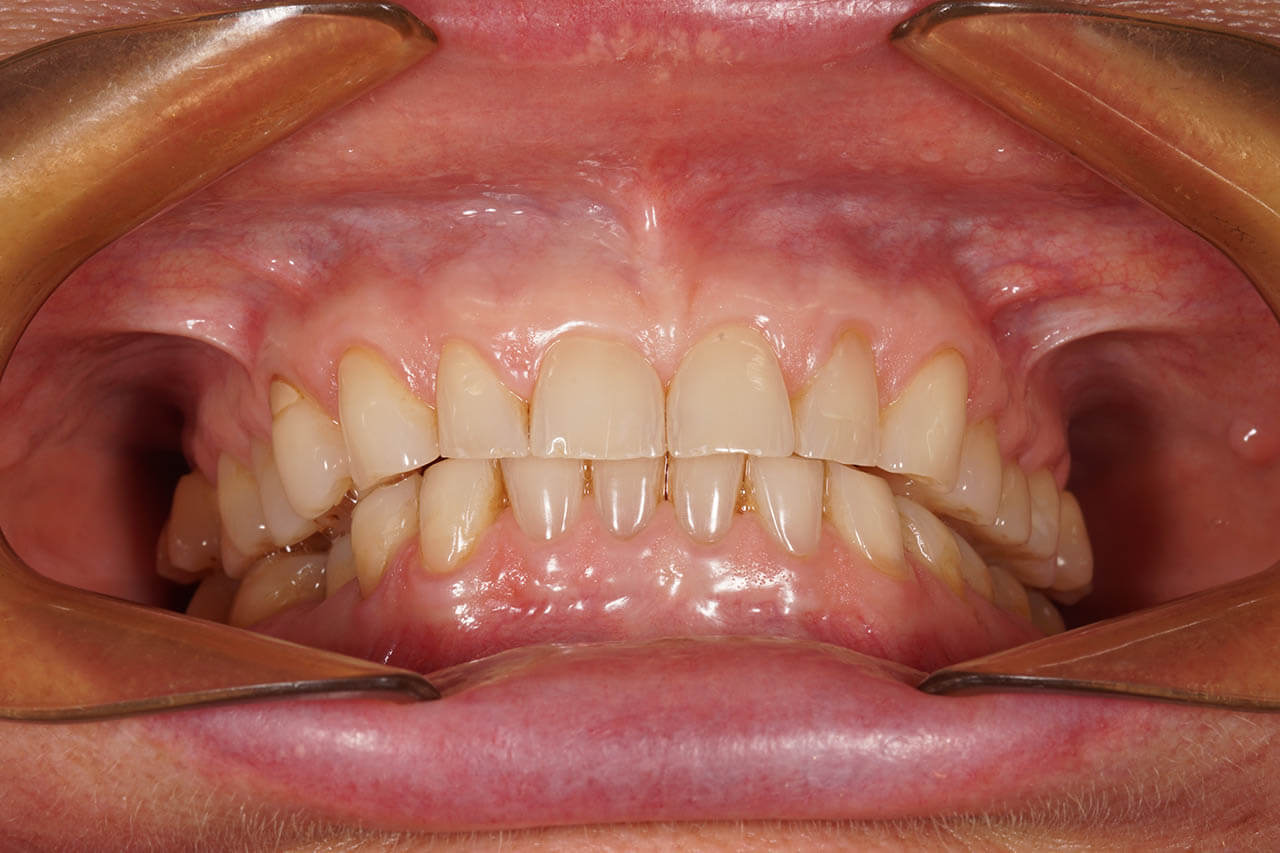

Dental prosthetics deals with filling gaps in the dentition and reconstructing damaged teeth. It is a good choice for anyone who in the past did not properly care for their teeth and as a result could not maintain their natural dentition or lost teeth due to illness or an unfortunate event. A properly chosen partial or full denture allows for the recovery of an aesthetic smile, good well-being, and self-confidence. Prosthetics at the Z Wieży clinic in Władysławowo offers you a wide range of modern prosthetic solutions, from which everyone can choose something tailored to their needs and expectations regarding the final result. Our experienced, highly qualified doctors are ready to provide assistance and good advice. To ensure the highest quality and aesthetics of restorations, we have for years cooperated with a renowned prosthetic laboratory.

Our prosthetic work

Dental prosthetics focuses on restoring missing teeth and reconstructing damaged ones.

CROWNS AND VENEERS

A beautiful, white smile brings more self-confidence and helps achieve success. It can be achieved, among others, through aesthetic medicine treatments or ortholifting.